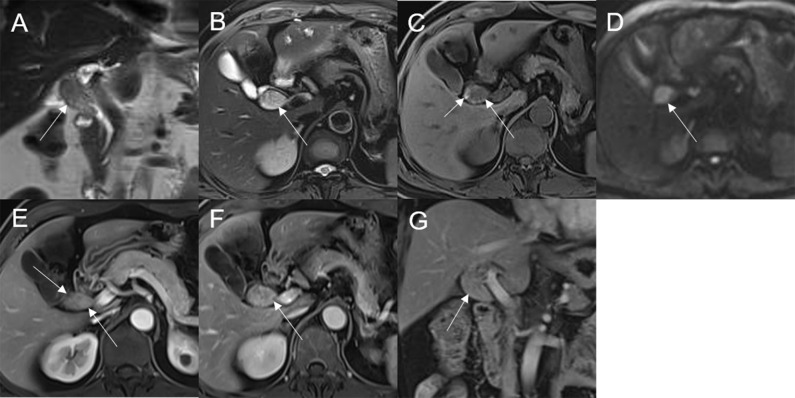

Mean lesion size in the whole sample was 30.83 ± 20.93 mm. All patients presented with an intraluminal ductal mass. While 14/32 (43.75%) lesions presented morphologically as focal eccentric-type masses (f3), 9/32 (28.13%) presented as plaque-like masses, 4/32 (12.50%) as bile duct casting masses, and 5/32 (15.62%) as infiltrative masses. In addition, 8/32 (21.88%) lesions showed a frond-like superficial appearance accompanied by other morphologically categorized appearances other than plaque-like superficial (f4, f5; T2).

Bile duct dilatation upstream of the lesion was present in all cases. Bile duct dilatation downstream of the lesion was present in 6/32 (18.75%) cases (f6) and at the lesion in 24/32 (75%) cases. In 8/32 (25%) cases, there was a stricture in the bile duct lumen at the lesion, along with an enlarged bile duct diameter; while four were cases of bile duct casting masses, the other four were cases of plaque-like masses.

In a previous imaging-based study, 60% of patients with extrahepatic bile duct adenoma had bile duct dilatation (ref. 11); however, the authors did not provide a detailed description of features of the dilated duct. In this study, bile duct dilatation was seen upstream of the lesion in all cases; while dilatation at the lesion site was common, dilatation downstream of the lesion was seen in only a few cases. Among the six cases with downstream bile duct dilatation, two lesions were secreting mucus with a doughy or jelly-like consistency, which may have blocked the distal bile duct. There have been previous reports of this phenomenon in patients with IPNB but not in patients with bile duct adenoma (ref. 19). Four of the six cases of downstream dilatation were in patients with multiple adenomas, with the dilatation being due to blockage of the bile duct by the distal lesion. Stricture of the bile duct lumen at the lesion site, with overall increase in bile duct diameter and upstream dilatation, was seen in all cases of bile duct casting masses and several cases of plaque-like masses. As mentioned earlier, in cases of plaque-like masses, bile duct dilatation at the lesion site was because of duct obstruction by lesions or secretions downstream.